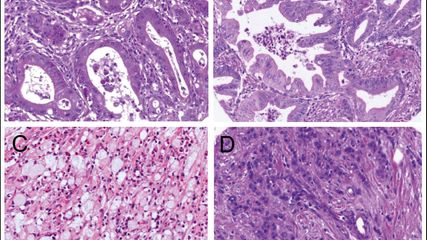

Abb. 1:Im Übersichtsbild kommt der kleine Knoten deutlich hervor. Maßstab 5000µm

Der ziliäre papilläre mukonoduläre Tumor der Lunge ist eine neue Entität, der eine charakteristische Morphologie aufweist (Abb. 1–4). Aufgrund der bisherigen Berichte kann von einer geringen Malignität ausgegangen werden. Die molekularen Signaturen lassen aber die Möglichkeit einer Rezidivierung und eventuell sogar einer Metastasierung offen.Dementsprechend kann eine Prognose nicht mit Sicherheit abgegeben werden. Eine engmaschige Kontrolle in den ersten fünf Jahre nach Diagnose ist zu empfehlen.